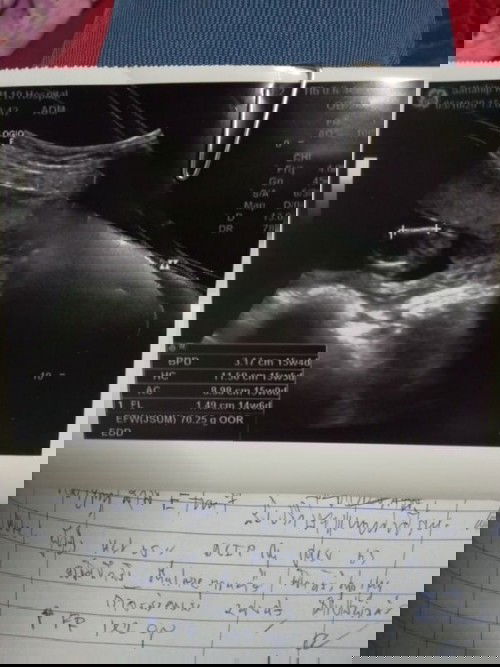

#ท้องแรกคะ เพิ่งไปซาวด์มา หมอบอกรกหนามาก ไม่สามารถคลอดเองได้ต้องผ่าอย่างเดียว กังวลมากค่ะ แม่ท่านไหนรกหนาเหมือนกันบ้างคะ